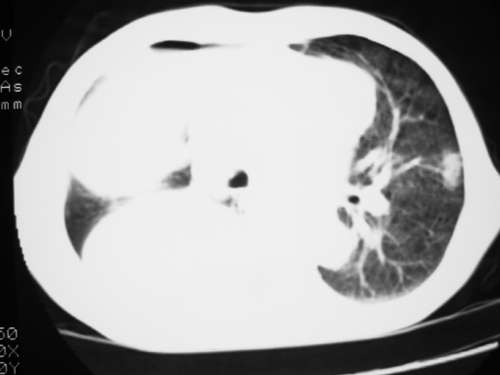

以下是引用yangyudong333在2008-4-29 5:46:00的发言:[br]1左上叶结节呈分叶状,边缘毛刺,考虑肺癌并纵隔淋巴结转移可能性大,结核待排,[br] [br]2右侧多发包裹性胸腔积液

以下是引用zsl6918在2008-4-29 9:15:00的发言:[br]右侧包裹性积液穿刺术后改变,肺内多发结节不除外转移可能。建议查胸水,问病史。